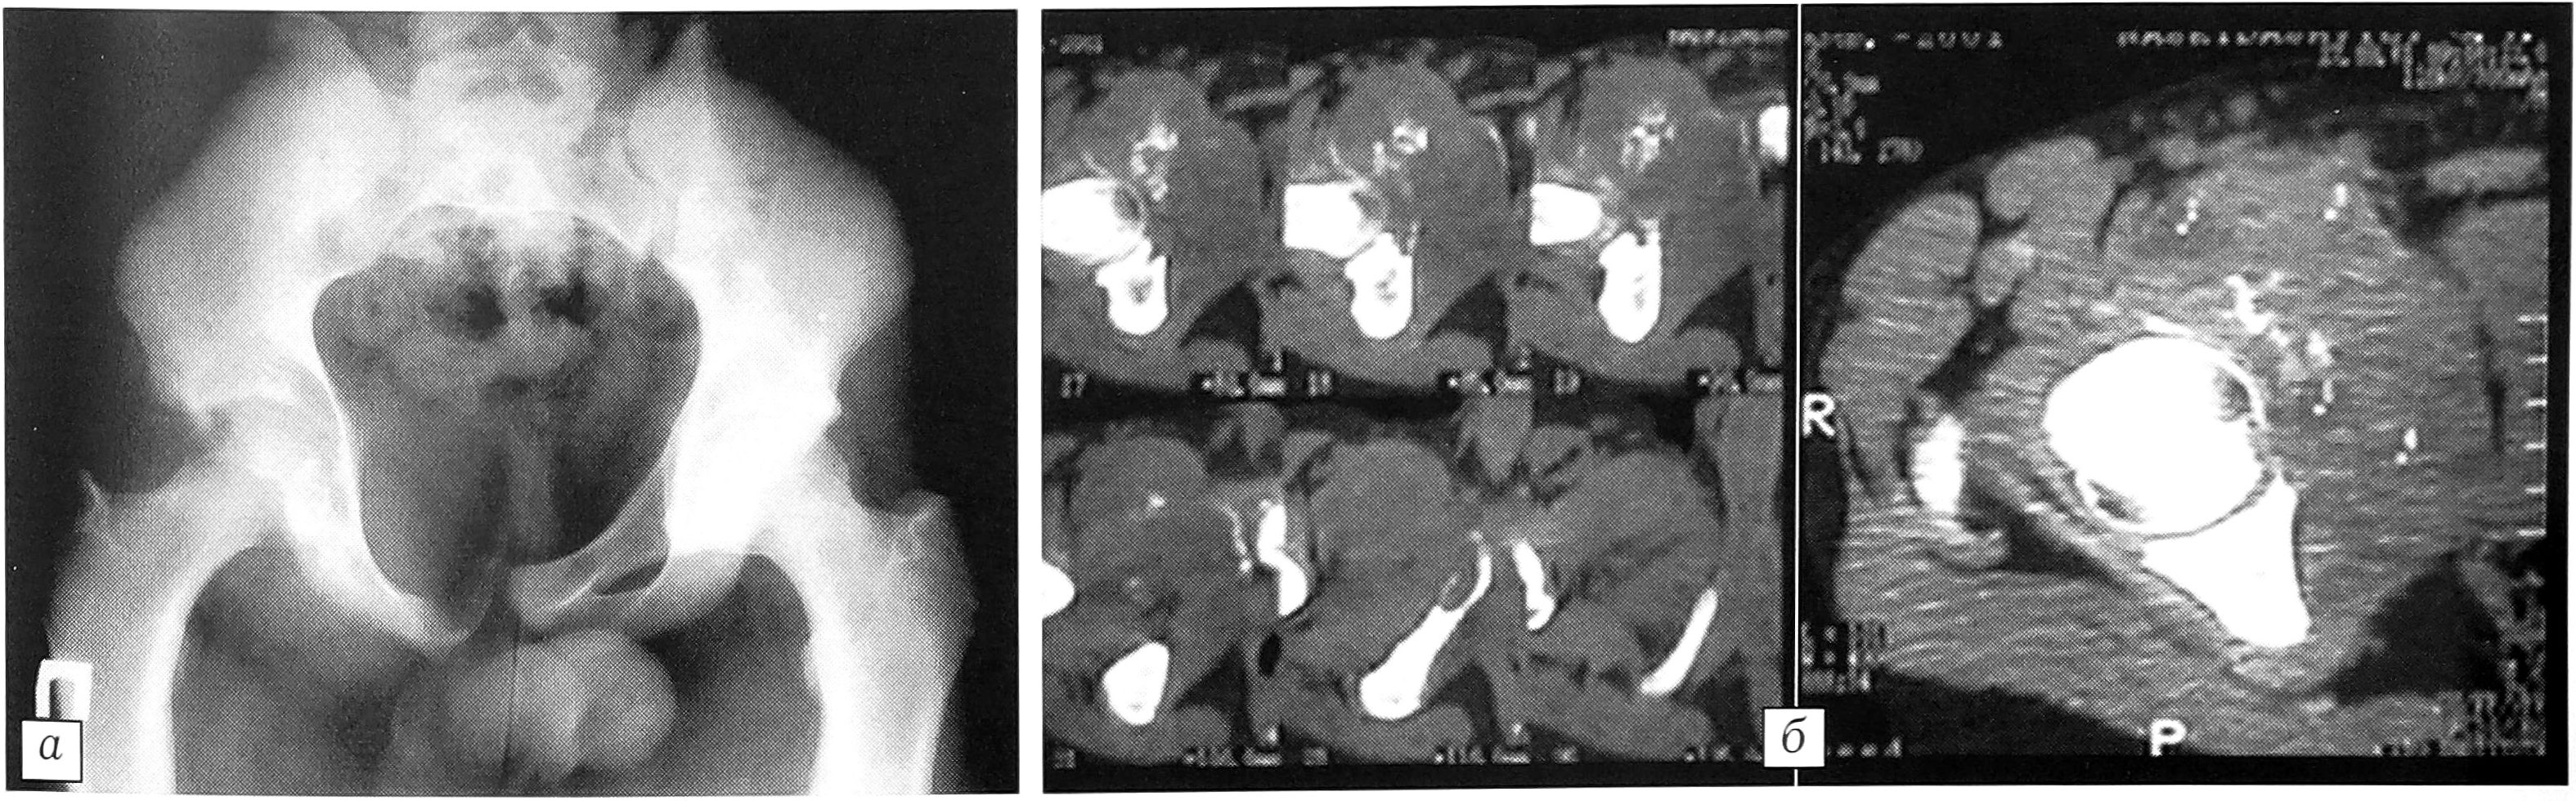

При лучевом обследовании (стандартная рентгенография, компьютерная томография) выявлен остеолитический очаг деструкции в верхней ветви лонной и в седалищной кости с разрушением коркового слоя и наличием мягкотканного компонента (рис. 1). Рентгенологическое заключение: аневризмальная киста или телеангиэктатический вариант остеосаркомы. С целью уточнения диагноза выполнена открытая биопсия правой лонной кости. Перед биопсией проведено измерение внутрикистного давления, которое составило 800 мм вод. ст. По данным гистологического заключения поставлен диагноз: активно растущая аневризмальная киста кости. Учитывая высокую активность кисты, выполнены три лечебные пункции очага (интервалы 7 дней) с промыванием полости кисты 5% аминокапроновой кислотой и введением 20 000 ЕД контрикала. Правый тазобедренный сустав иммобилизован тазобедренной гипсовой повязкой.

Рис. 1. Рентгенограмма таза (а) и компьютерная томограмма (б) при поступлении больного: остеолитический очаг деструкции с поражением лонной и седалищной костей справа.